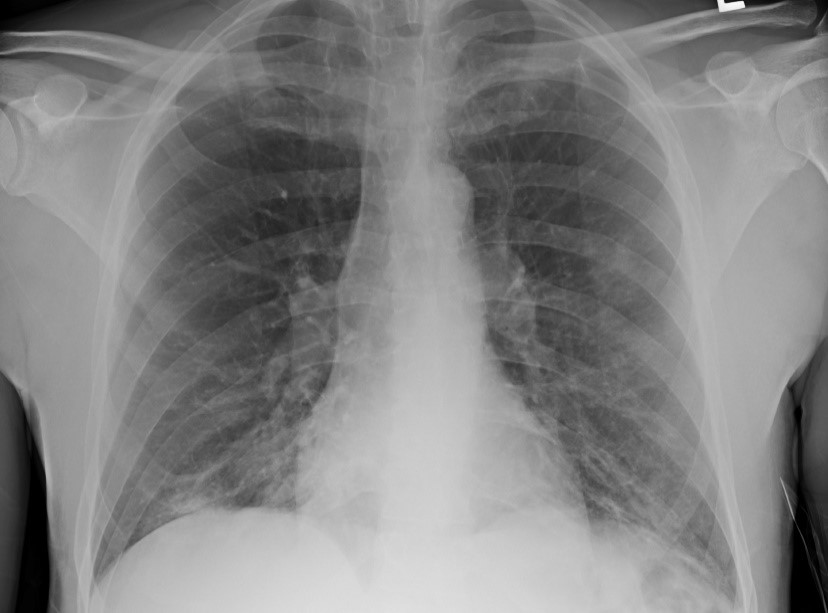

The patient was diagnosed with diabetic ketoacidosis (DKA) and was started on intravenous fluids and insulin. An infectious workup was initiated to identify a possible precipitating etiology. The procalcitonin level was 0.30 ng/mL (<0.50 ng/mL indicates that systemic infection is less likely), results of a standard respiratory viral panel were negative, urinalysis findings were unremarkable, and urine Streptococcus pneumoniae and Legionella antigen test results were negative. However, a chest radiograph revealed patchy bibasilar opacifications (Figure).

Figure. The patient’s chest radiograph showing patchy bibasilar opacifications.

The findings in this patient’s case suggest that COVID-19 may have precipitated DKA. While the patient presented with symptoms of hyperglycemia and cough, chest radiography findings were concerning for COVID-19. Common abnormal radiographic features in a COVID-19–positive patient include consolidation or ground-glass opacities with bilateral, peripheral, and lower lung field distribution. These findings may be less noticeable or absent in early or mild disease but tend to increase over the course of the illness.4